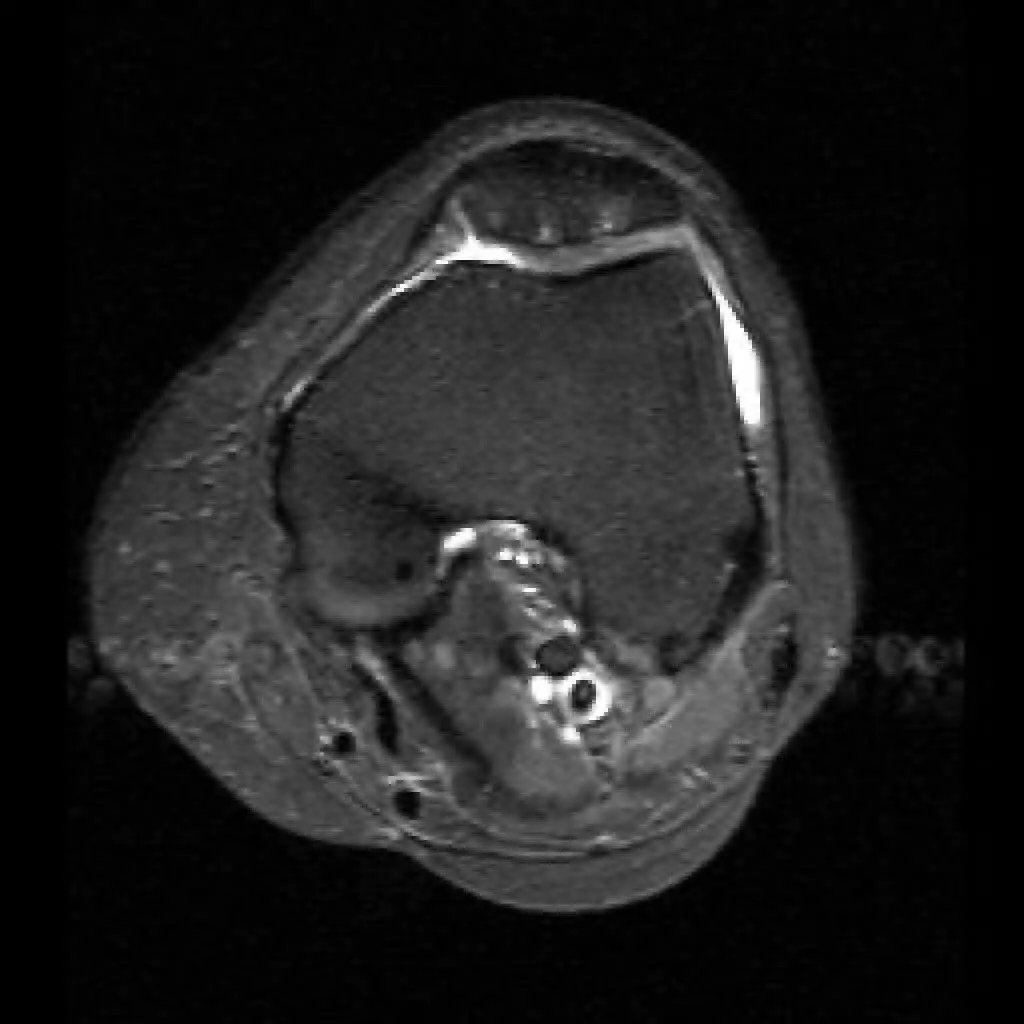

Артрит колінного суглоба, кіста Бейкера (МРТ).

МРТ коліна дозволяє бачити тонкощі і особливості ушкодження тканини коліна, наприклад при травмі (меніски, зв’язки, скриті переломи кісток і багато іншого).

МРТ колінного суглоба (фото 1)

МРТ суглобів, читати більше.